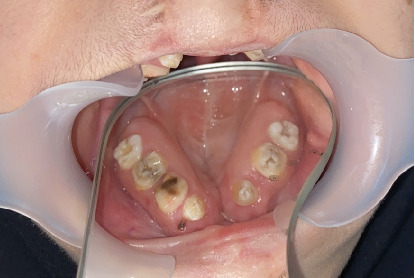

Background: Cleft lip and palate require complex treatment, often involving early surgery. Postoperative complications, such as palatal fistulas, can impair speech and feeding. While surgical correction is standard, large fistulas may pose challenges due to age, cost, and recurrence risks. Obturator prostheses provide a nonsurgical alternative, but digital impression techniques for their fabrication are underutilized. This case report explores intraoral digital impressions for creating obturator/speech aid appliances in a patient with cleft palate deformities. Methods: A 17-year-old female with Class III malocclusion on a Class III skeletal base and increased facial proportion and IOFTN score of 5, with cleft palate-related eating difficulties, missing anterior teeth, and worn dentition, underwent intraoral scanning. Digital files were used to fabricate a premolar-to-premolar obturator, with relief areas and teeth arranged on printed casts. Results: The appliance effectively addressed functional and aesthetic concerns. Conclusion: Digital impressions offer precise, efficient, and comfortable fabrication of obturator prostheses compared to conventional methods. Despite initial costs, they reduce chair time, enhance accuracy for dental hard tissues, and improve patient experience, particularly for young patients with cleft lip and palate.